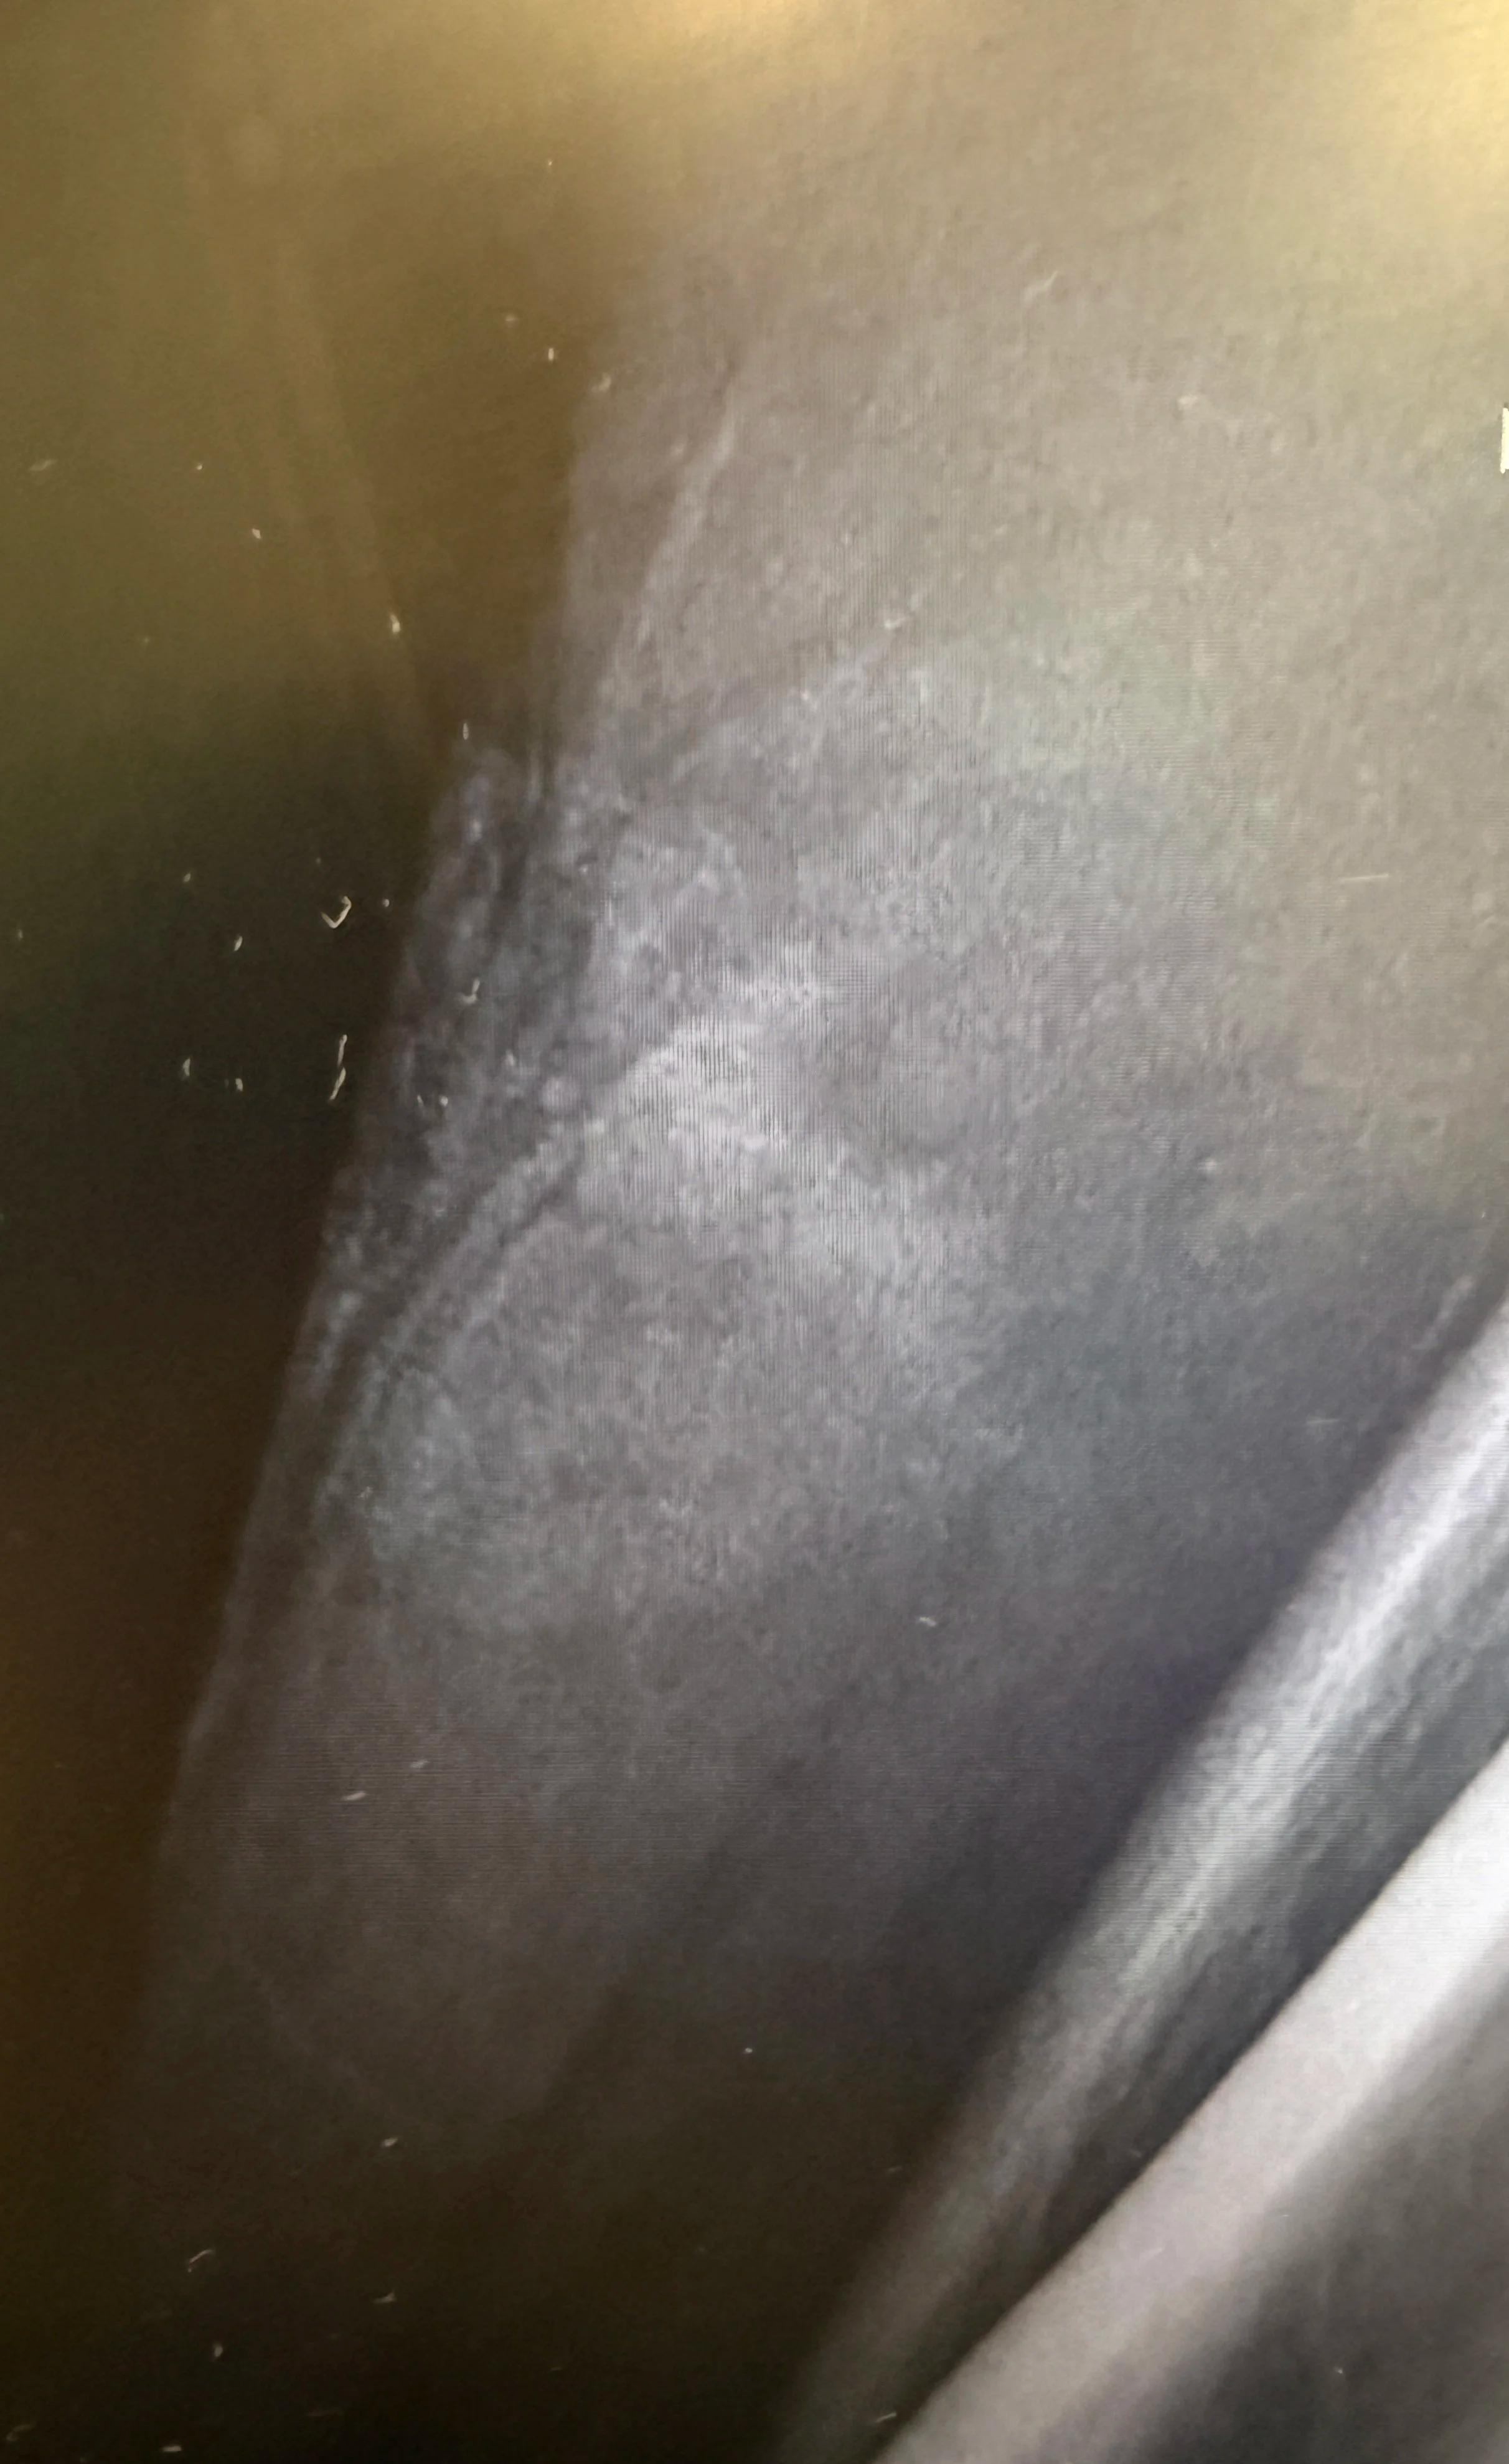

In the case shown here, a V-shaped flap laceration of the lower extremity was closed using a combination of vertical mattress sutures across the flap and simple interrupted sutures for the remaining wound.

• Vertical mattress sutures: Ideal for areas of high tension. They provide eversion of wound edges, distribute force deeper in the dermis, and reduce the risk of inversion that compromises vascularity. They also relieve pressure from the fragile flap tip.

• Simple interrupted sutures: Still the backbone of laceration repair. They allow for precise edge approximation and are forgiving if infection develops, since a single suture can be removed without compromising the entire closure.

Pearl: Always assess the flap tip for perfusion after placement of tension-relieving sutures. If blanching persists, consider loosening or revising your approach. Overzealous tension can strangle the very tissue you are trying to preserve.

Flap Closure may take a combination of sutures.

Modified or vertical mattress are great for tension relief.

Consider adding simple interrupted sutures to bring It all together.

Bandage with anti-bacterial ointment and a non-adhesive dressing with suture removal in 10-12 days.